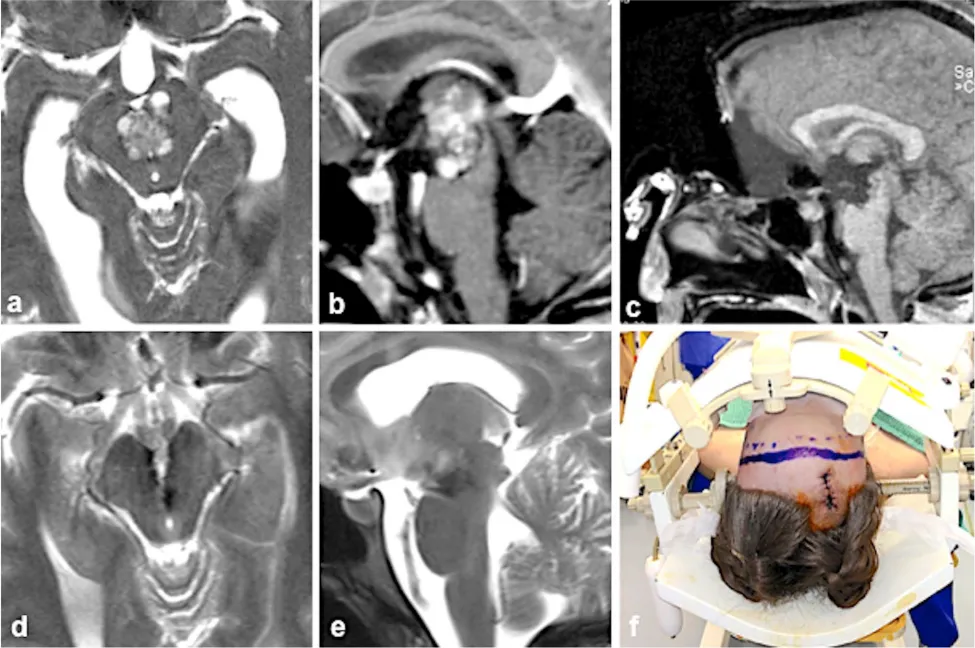

病例一:21岁女性患者

患者因短暂性动眼神经麻痹就诊。MRI检查发现中脑海绵状血管瘤(图a),病灶向上延伸至丘脑,顶部抵达第三脑室底部(图b)。畸形血管瘤出血导致梗阻性脑积水,引发复视、严重头痛及呕吐等症状。通过前纵裂入路(图f)成功切除中脑海绵状血管瘤(图c、图d、图e)。术后患者动眼神经麻痹症状出现短暂性轻度加重,但3个月内完全恢复正常。